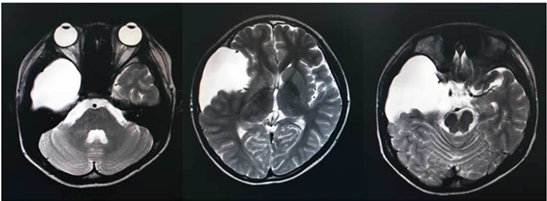

In August, an unintended MRI of the head revealed a large arachnoid cyst involving the whole right temporal lobe (Figure 1). But no markable findings in neurologic and physical examinations. The results of basic laboratory workups, including CBC, serum chemistry, TSH test, were all within normal limits.

Figure 1 T2-weighted MRI showed an arachnoid cyst over the entire right temporal lobe.